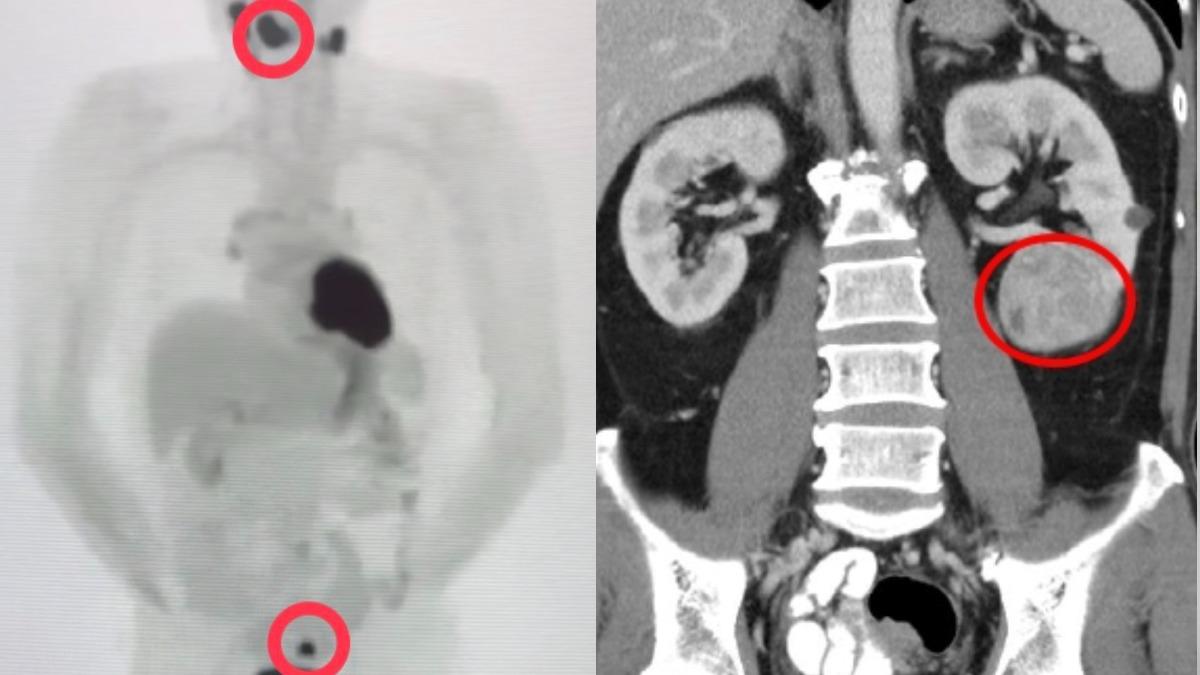

據了解,卓男過去曾有高血壓、糖尿病與B型肝炎,父親罹患胃癌、母親則是腦癌,平時卓男不僅每天喝酒吃檳榔,還會抽掉半包菸,即便每天有運動習慣,只是他仍於2024年4月出現喉嚨痛狀況,且到診所反覆看了3、4次,依舊沒有改善。於是卓男2024年12月9日轉到榮總治療,先是被查出第3期舌癌,接著再發現大腸、左腎及甲狀腺3處腫瘤,且特別的是,卓男並非單一癌症轉移,而是4個獨立病灶,同時確診第1期大腸癌、第2期腎臟癌和第1期乳突甲狀腺癌。

林俊余也表示,1人同時罹患4種原發性癌症的機率極為罕見,發生率低於0.1%,多重原發性癌症原因可能和遺傳風險因子或癌前病變體質有關,環境因素也需考量,目前卓男4癌症定期追蹤,生活恢復如常,正在戒菸並運動,維持健康生活。